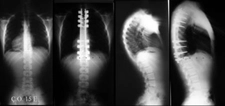

Skolyozun tanısı genellikle fizik muayene ve görüntüleme yöntemleri ile konulur.

• Fizik muayene sırasında doktor, omurganın görünümünü değerlendirir ve belirtileri inceler.

• X-ray, skolyozun derecesini belirlemek için en yaygın kullanılan görüntüleme yöntemidir.

• Gerekirse, MRI veya CT taramaları ile daha detaylı bilgi edinilebilir.

Bu yöntemler, skolyozun ciddiyetini ve tedavi gereksinimlerini belirlemede kritik öneme sahiptir.

• Cerrahi müdahale: Şiddetli skolyoz vakalarında, omurganın düzeltilmesi için cerrahi operasyon gerekebilir.